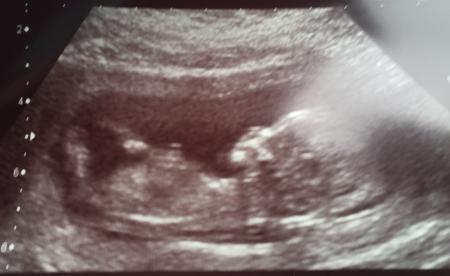

Hallo Wir hatten heute das Screening und alles sah gut aus, ist ein ziemlicher Windfang und hat nur rumgeturnt Lg Monique

Bild zu First Trimester Screening - Forum für August - Mamis

Und echt schöne Bilder! Man kann so richtig gut das Gesicht erkennen.